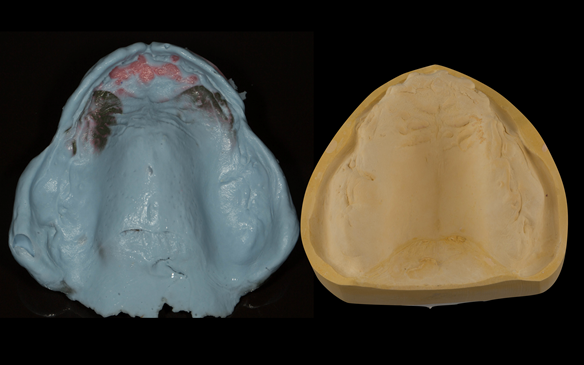

This newsletter describes in step by step detail the transition from acrylic based immediate dentures to metal based definitive dentures.

- Reviews of the immediate dentures and relines as needed over 9 - 12 months

- Definitive dentures (Mk 2) – complete upper metal reinforced and lower cobalt chromium based partial of hygienic Scandinavian design to be made 9 - 12 months after extractions of all upper teeth and LR5 and LL4